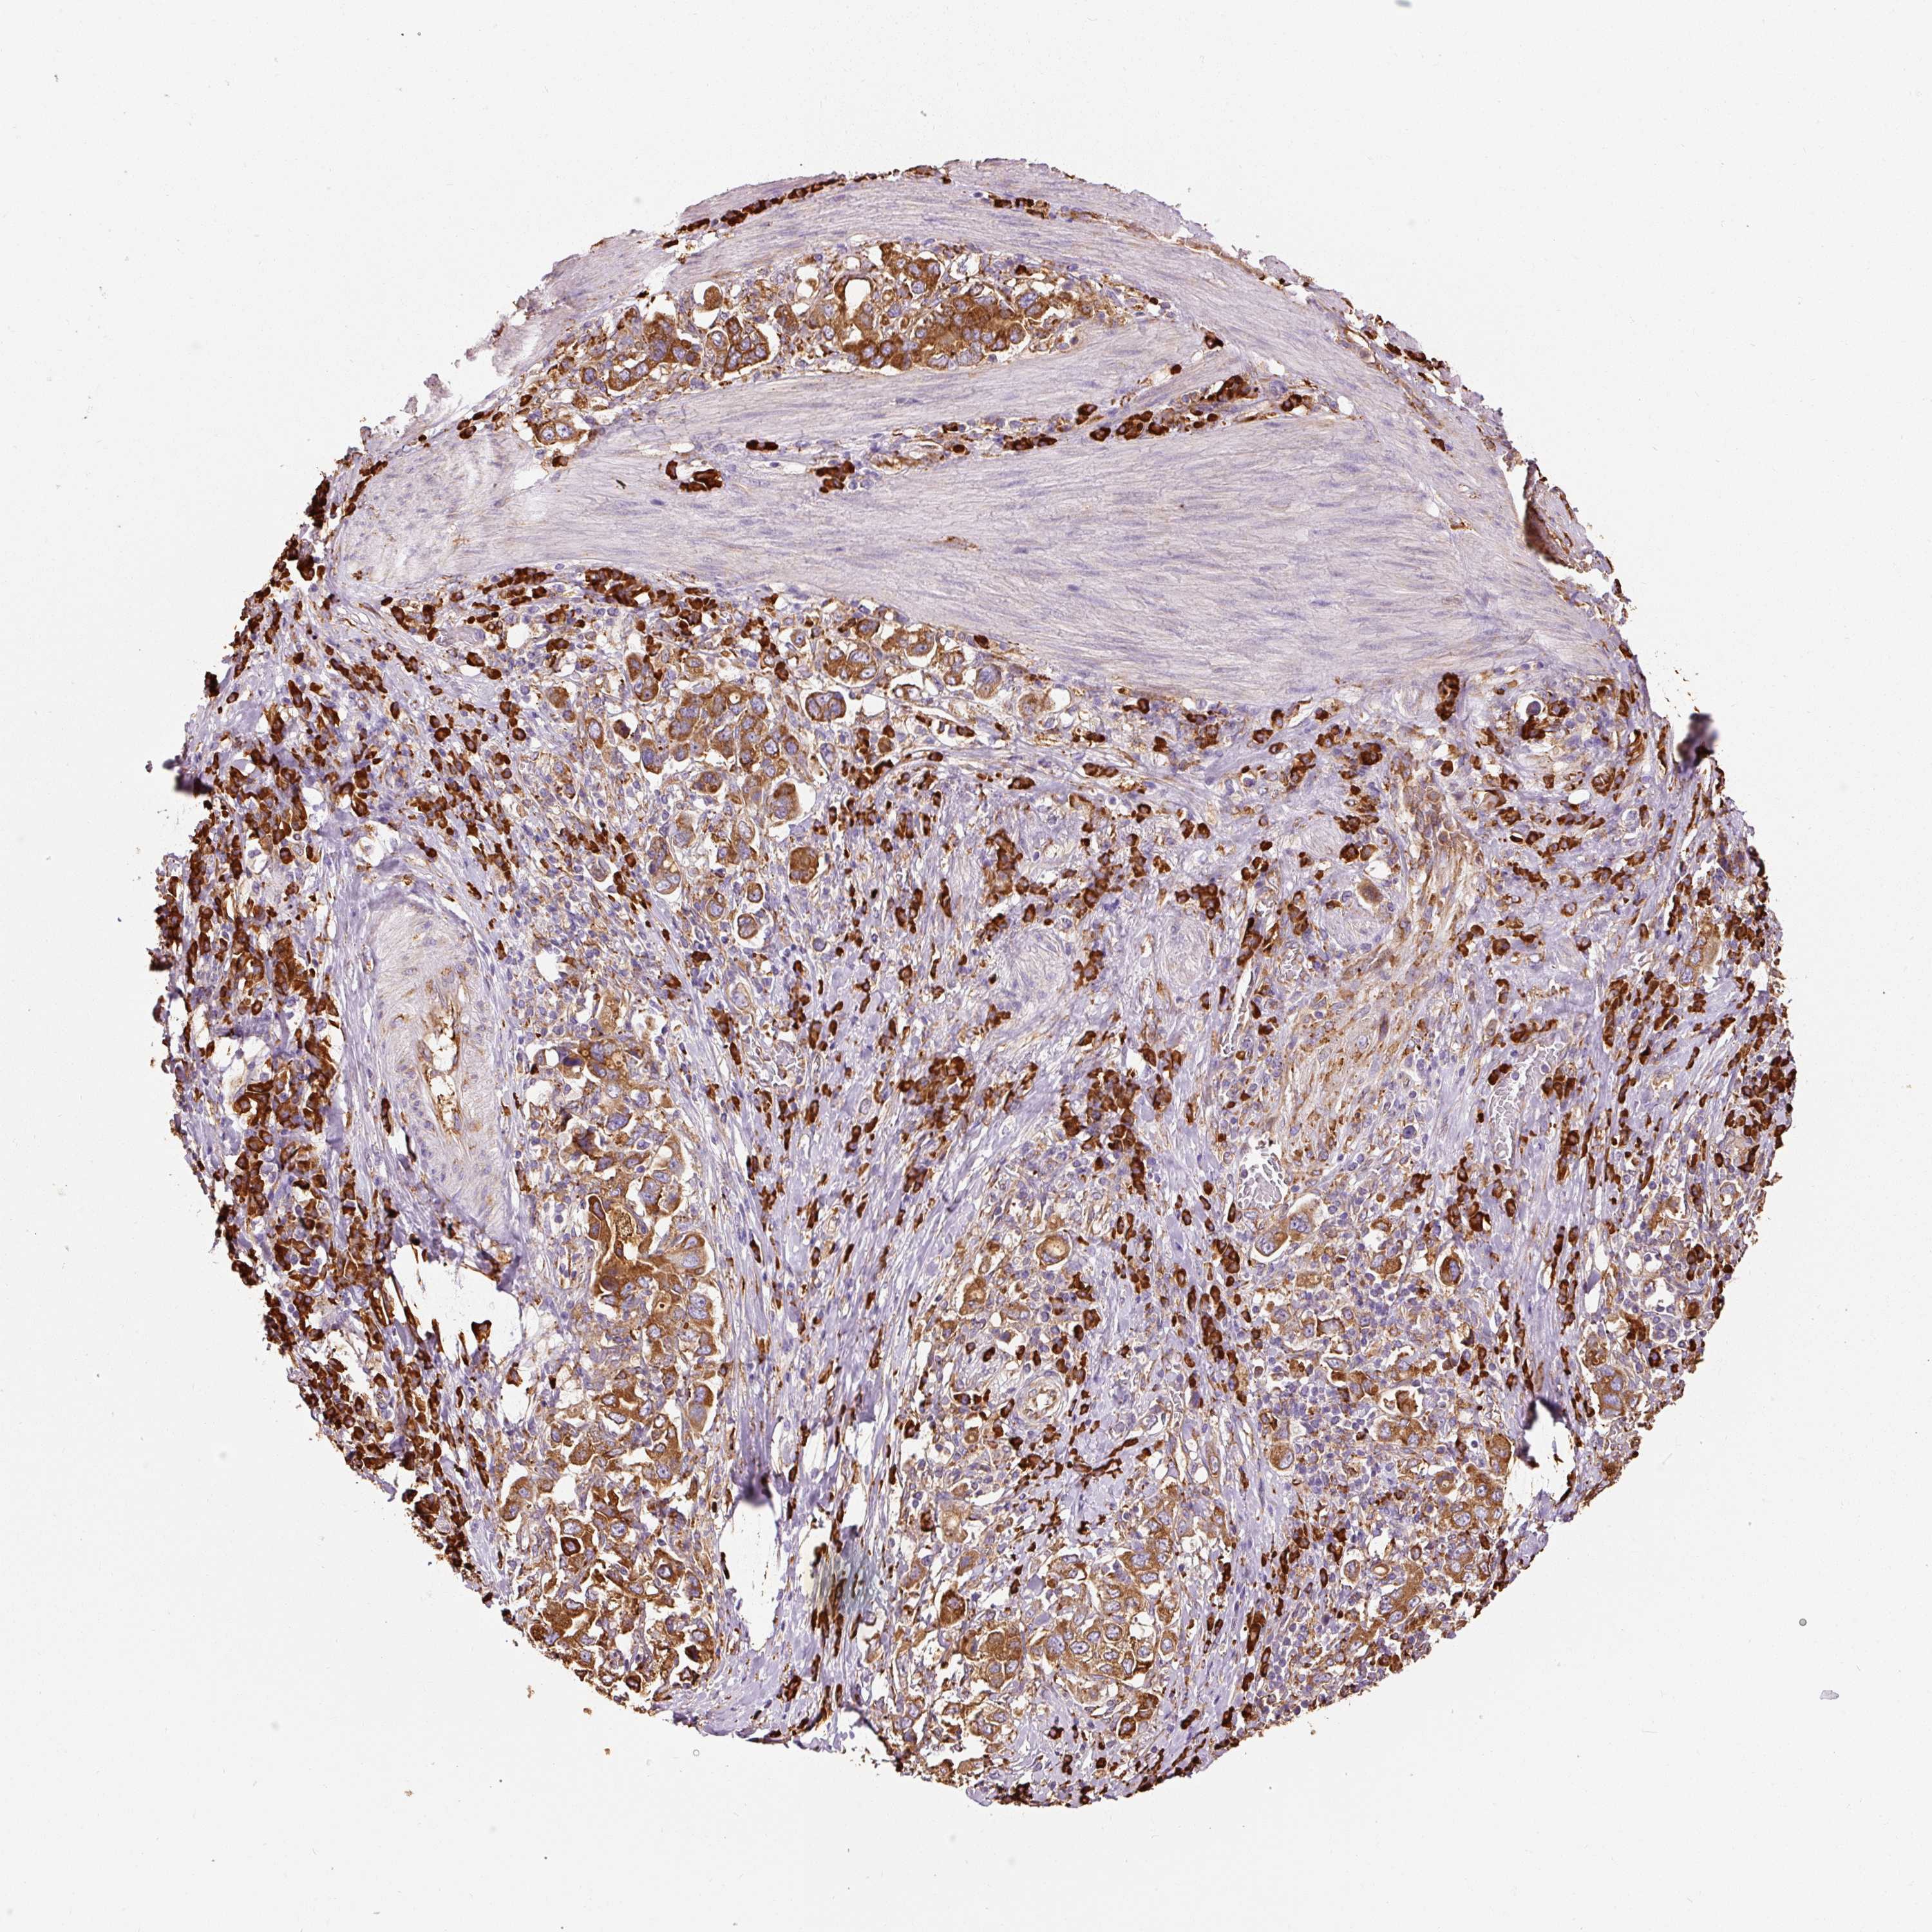

STOMACH CANCER - Protein expressioni

A mouse-over function shows sample information and annotation data. Click on an image to view it in a full screen mode. Samples can be filtered based on level of antibody staining by selecting one or several of the following categories: high, medium, low and not detected. The assay and annotation is described here.

Note that samples used for immunohistochemistry by the Human Protein Atlas do not correspond to samples in the TCGA dataset.

Antibody stainingi

Antibody staining in the annotated cell types in the current human tissue is reported as not detected, low, medium, or high, based on conventional immunohistochemistry profiling in selected tissues. This score is based on the combination of the staining intensity and fraction of stained cells.

Each image is clickable and will lead to virtual microscopy that enables deeper exploration of all samples and also displays staining intensity scores, fraction scores and subcellular localization as well as patient and tissue information for each sample.

Antibody HPA044617

Antibody HPA052450

Staining

High

Medium

Low

Not detected

Intensity

Strong

Moderate

Weak

Negative

Quantity

>75%

75%-25%

<25%

None

Location

Nuclear

Cytoplasmic/membranous

Cytoplasmic/membranous,nuclear

Adenocarcinoma, NOS